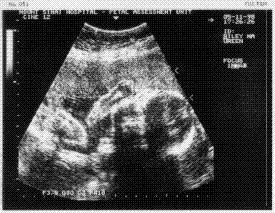

(Here is an image of Baby "A"

from Nov. 5, lying sideways, head on the right and body on the left.

An arm is visible above the head.) |